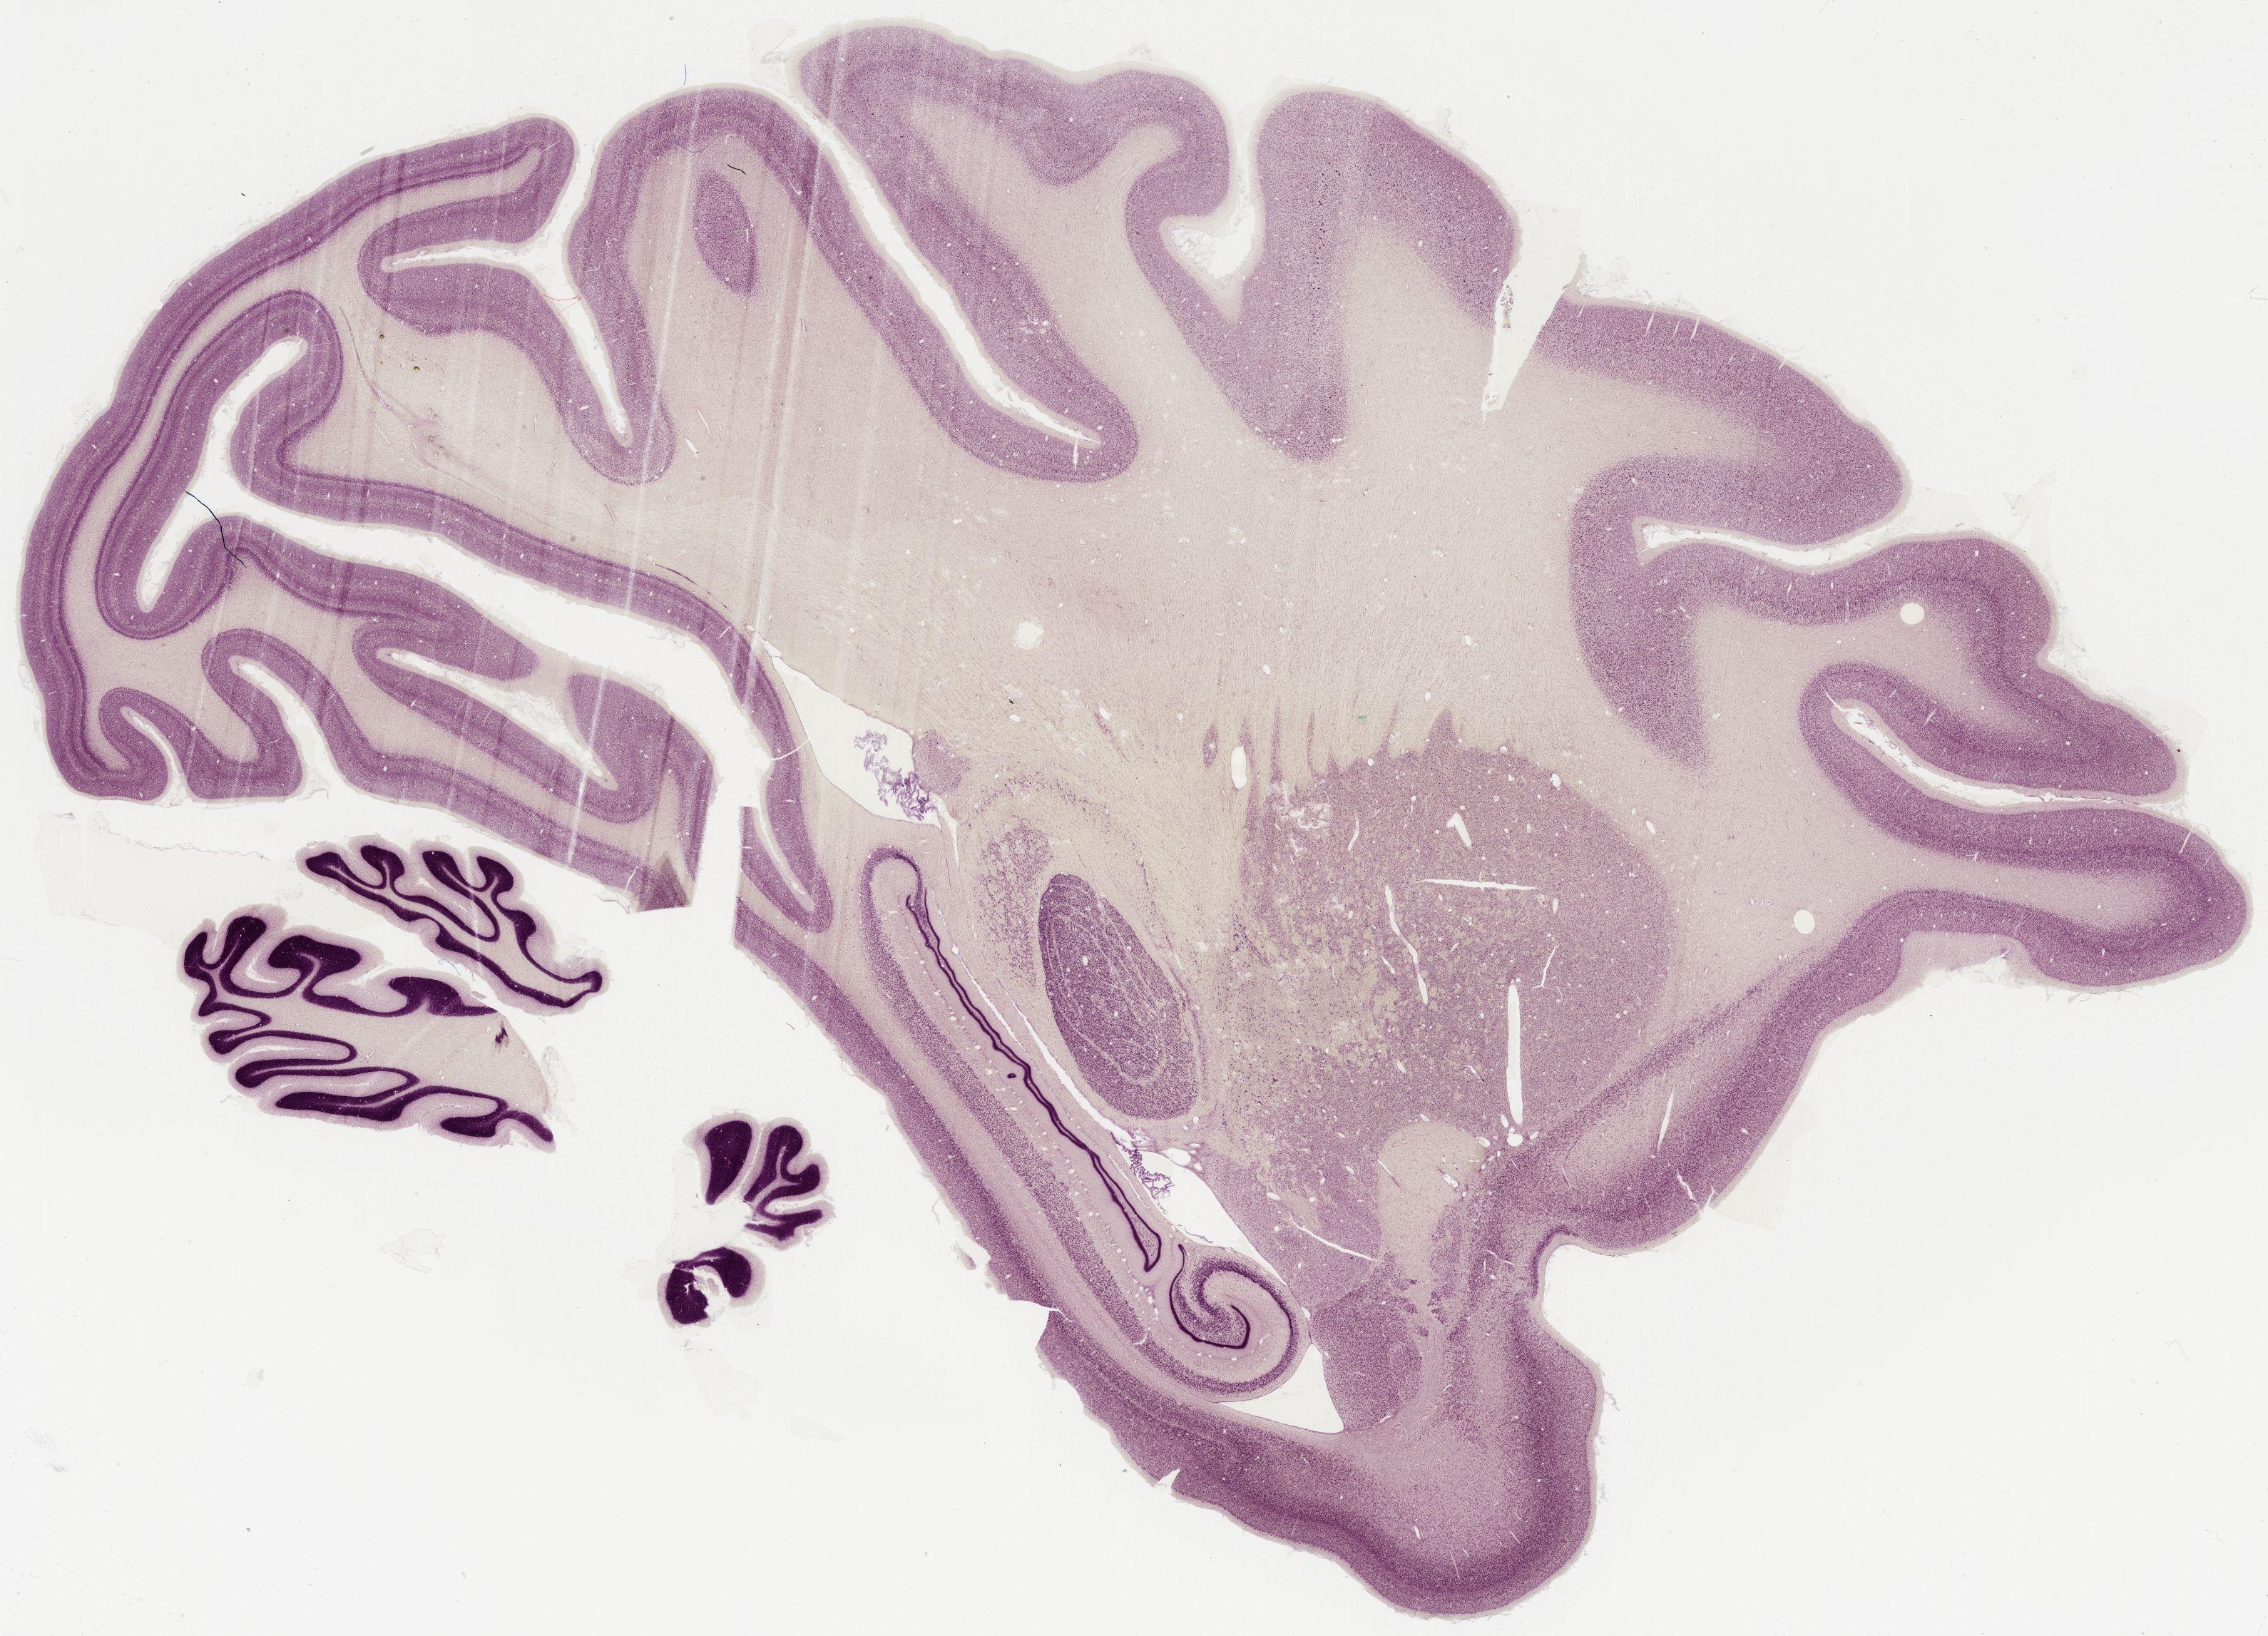

Datasets -> Macaca Mulatta -> Nissl, sagittal, histo, Whole-Brain, adult

[ Metadata ]   ·   Source: Edward G. Jones